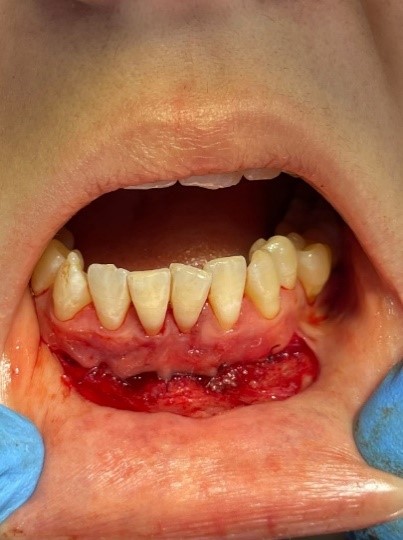

Клинический случай № 2. Пациентка 28 лет находится на ортодонтическом лечении. Пришла на прием по рекомендации врача-ортодонта. Осмотр преддверия полости рта показал недостаточное количество прикрепленной десны во фронтальном отделе нижней челюсти. Констатировано мелкое преддверие полости рта, 3 мм прикрепленной десны (рисунок 3a). Рекомендовано углубление преддверия путем вестибулопластики. Сопутствующие соматические заболевания отрицает. Результаты общего анализа крови без видимых патологий.

Проведена операция по углублению преддверия полости рта по Эдлану – Мейхеру. Рассечение и смещение мышечных тяжей апикально (рисунок 3b). Наложение швов с фиксацией слизистого лоскута к надкостнице (рисунок 3c). После снятия швов даны рекомендации (рисунок 3d).

a

b

c

d

Рис. 3. Мелкое преддверие полости рта: a – мелкое преддверие; b – смещение мышечных тяжей апикально; c – фиксация слизистого слоя к надкостнице; d – углубленное преддверие полости рта

Fig. 3. Small Oral Vestibule: a – small vestibule; b – pical displacement of muscle strands; c – fixation of the mucous layer to the periosteum; d – the deepened vestibule of the oral cavity